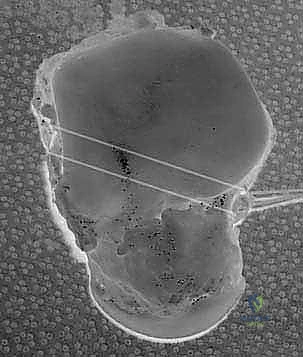

2. الفحص بالمنظار (Arthroscopy)

كخطوة أولى، ولضمان الدقة القصوى، غالباً ما يستخدم الدكتور هطيف منظار الكاحل عالي الدقة (4K Arthroscopy). يتم إدخال كاميرا دقيقة جداً عبر شقوق صغيرة (ثقوب) لفحص مفصل الكاحل من الداخل، تنظيف أي أنسجة ملتهبة، ومعالجة أي تلف في الغضاريف قد يكون مصاحباً للإصابة.

5. حفر الأنفاق العظمية وإعادة البناء (Bone Tunnels & Fixation)

هذه هي الخطوة الأكثر دقة هندسياً في الجراحة:

* يتم حفر أنفاق دقيقة جداً في عظمة الكعب الإنسي (قصبة الساق) وفي العظم الكاحلي وأحياناً العظم العقبي، وذلك في نفس نقاط الارتكاز التشريحية للرباط الدالي الأصلي.

* يتم تمرير الطعم الوتري عبر هذه الأنفاق بطريقة تحاكي تماماً شكل ووظيفة الأربطة العميقة والسطحية.

* يتم شد الطعم للدرجة الميكانيكية المثالية التي تضمن استقرار الكاحل دون تقييد حركته الطبيعية.

* يتم تثبيت الطعم بقوة داخل العظام باستخدام مسامير تداخلية (Interference Screws) أو خطاطيف معدنية/بلاستيكية قابلة للامتصاص (Suture Anchors) من أحدث الطرازات العالمية.